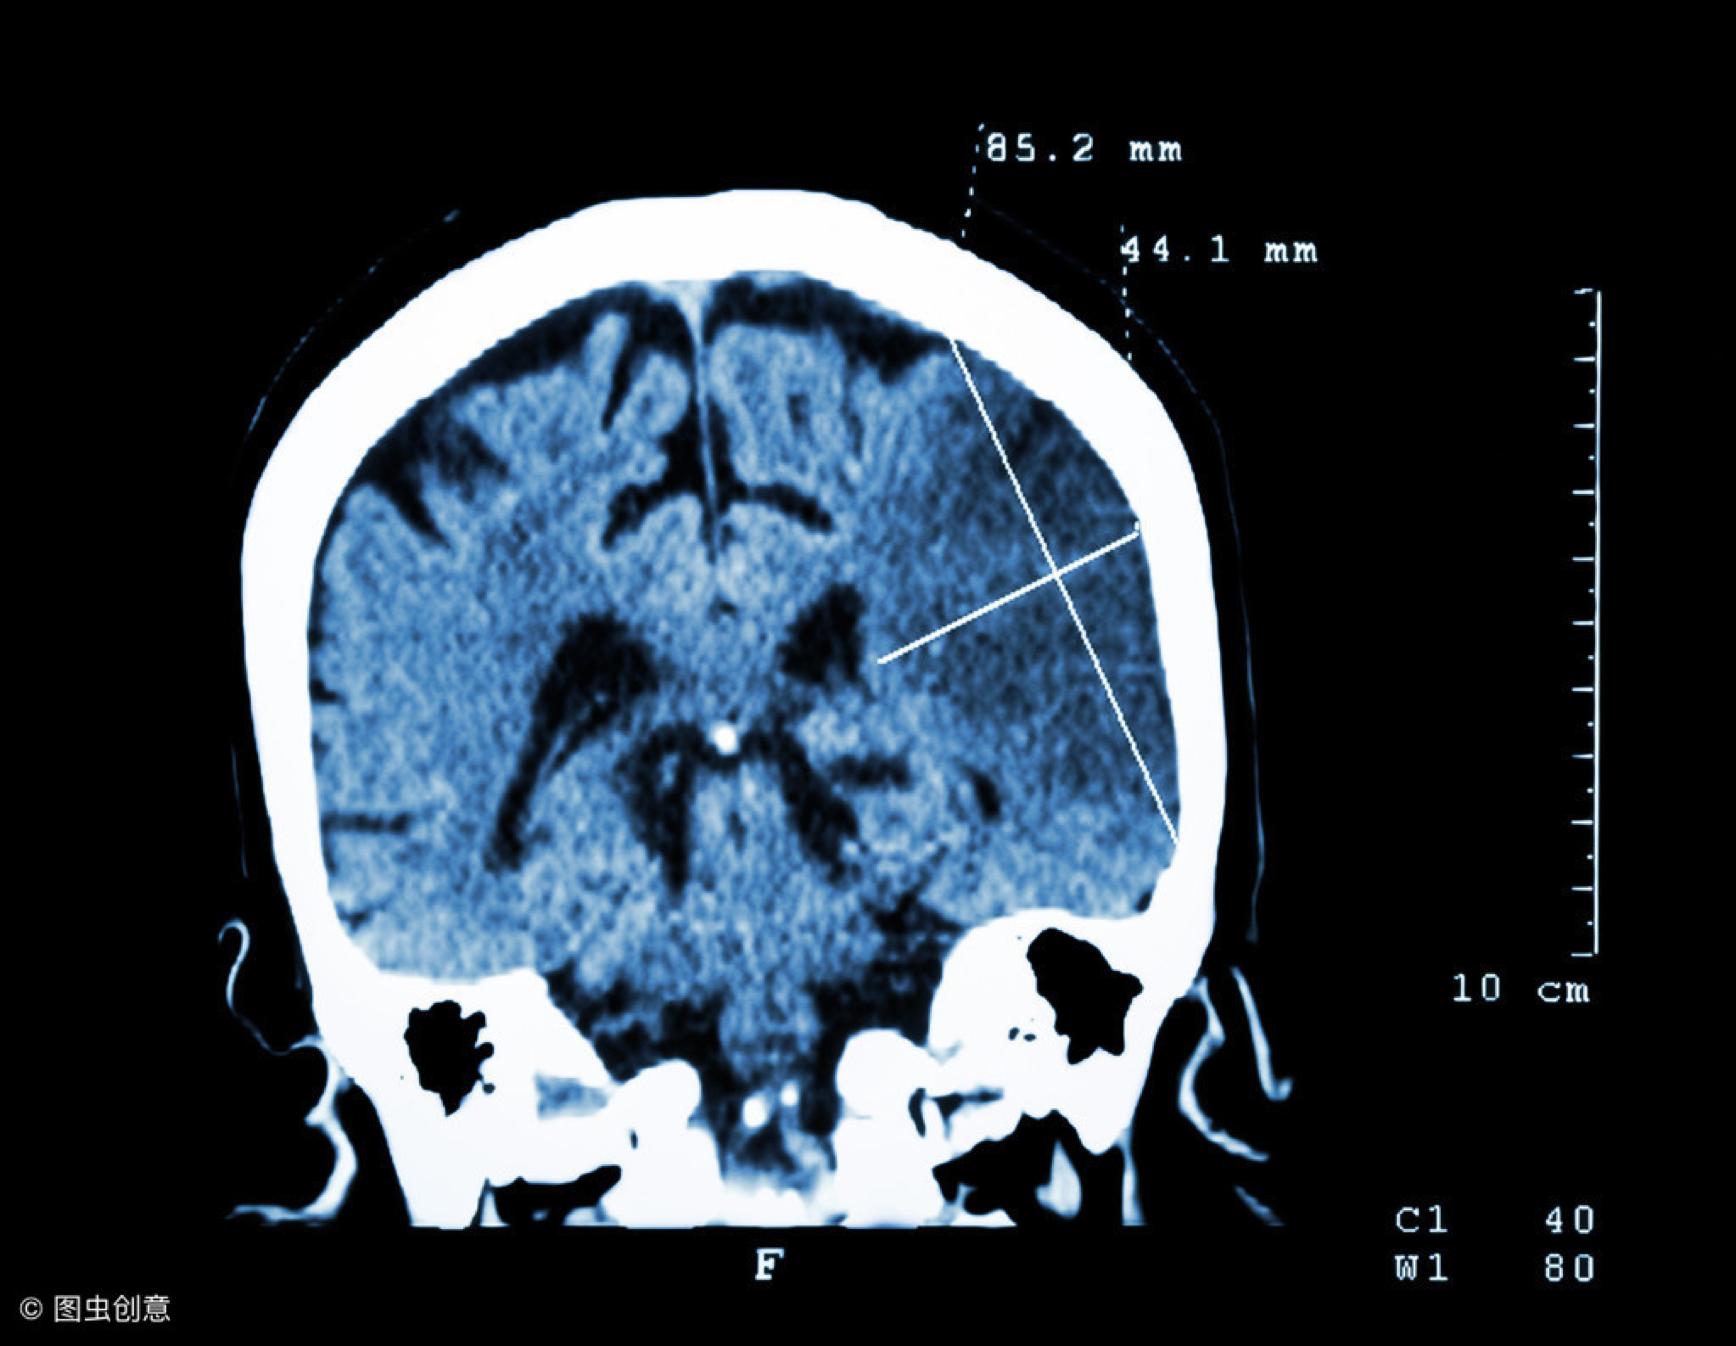

“高患病率、高死亡率、高复发率”是脑梗“三高”特征。

据数据统计:我国每年新发心脑血管疾病患者,高达200万人,总患病人数已破500万,其中脑梗约占65%左右。